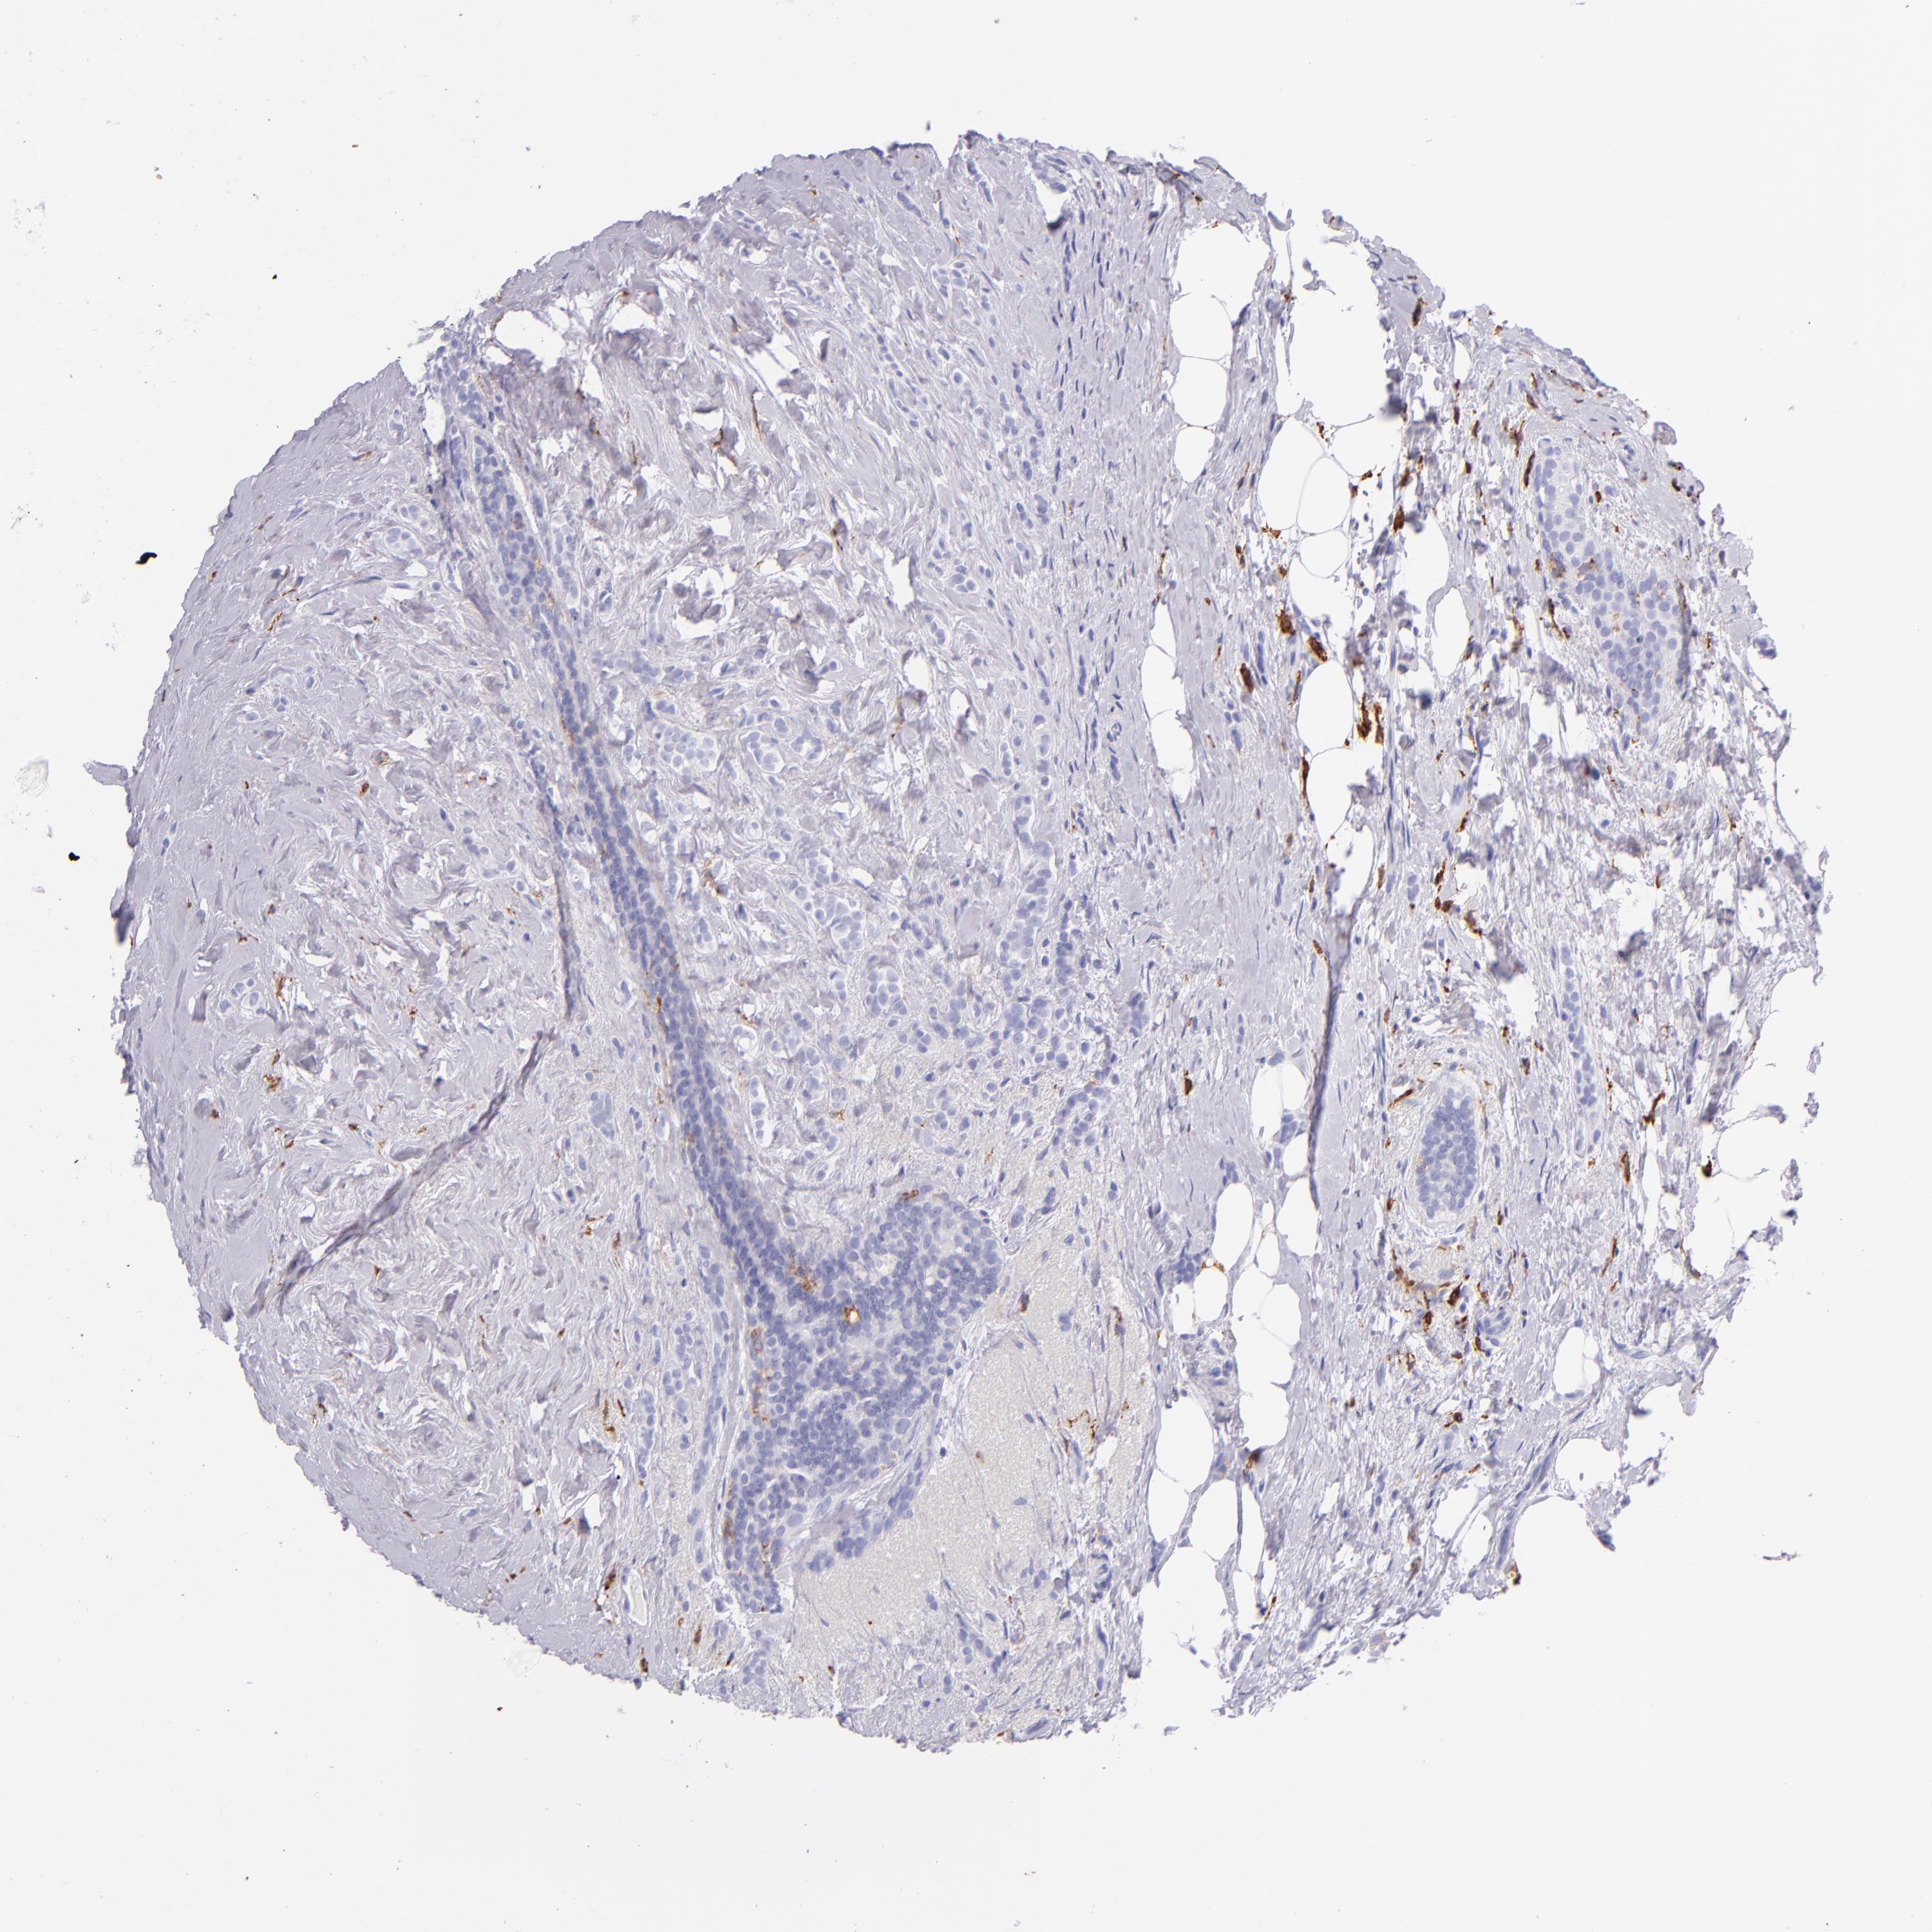

CD163

CANCER BREAST CANCER Show tissue menu

BRCA TCGA BRCA VALIDATION PROTEIN EXPRESSION